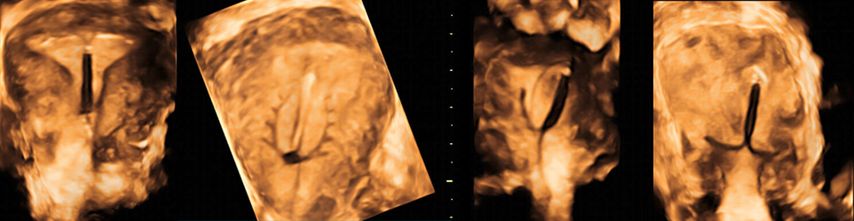

Bei unklar liegenden Intrauterinpessaren oder «lost threads» ermöglicht sie die Darstellung des Fremdkörpers im Cavum. Fehllagen von Kupfer- und Hormonspiralen (z.B. «upside-down IUD») können so schnell und exakt diagnostiziert und der Patientin demonstriert werden (Abb. 7).

Abb. 7: 3D-sonografische Darstellungen von Intrauterinpessaren. Neben einem korrekt (hoch fundal) liegenden Pessar (links) zeigt das Bild fehlliegende Kupfer- und Hormonspiralen (Korpus, Ärmchen, Faden)